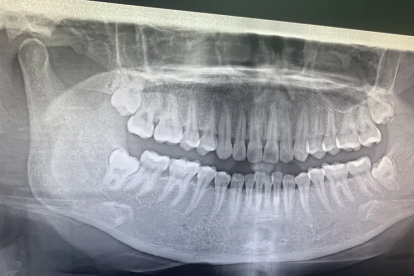

智齿破了一半通常建议拔除。智齿部分破损可能导致食物嵌塞、细菌滋生或邻牙损伤,增加龋齿、牙龈炎等口腔疾病风险。

智齿破了一半时,残留的牙体结构可能形成尖锐边缘,容易划伤口腔黏膜或舌头。破损部位容易堆积食物残渣,清洁困难,长期可能引发智齿冠周炎,表现为牙龈红肿、疼痛甚至化脓。部分破损的智齿若位置不正,可能倾斜生长压迫邻牙,导致第二磨牙龋坏或牙根吸收。对于已经出现反复感染、邻牙损伤或咬合干扰的情况,拔除是更彻底的治疗方案。

若智齿破损后无感染症状且位置端正,可暂时观察。但需加强口腔清洁,使用冲牙器清理破损处,定期口腔检查监测变化。孕妇、高血压或糖尿病患者等特殊人群需评估全身状况后再决定是否拔牙。对于完全埋伏且无症状的破损智齿,可能无须立即处理。